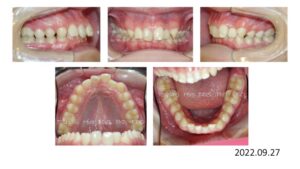

まずは、下顎前突です。

13歳の女の子、反対咬合と叢生を主訴に来院されました。

チンキャップで下顎の成長抑制を行いつつ、上顎両側5番、下顎両側4番を抜歯し、上下顎にブラケットを付け、

下顎前歯部をリトラクションし、反対咬合を改善し、ここから細かな調整に入ります。

治療が終わりました。

動的治療期間は 1年 9か月です。